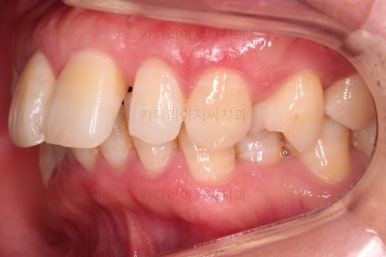

마무리 사진이에요.

치열이 매우 가지런해졌고, 틈도 없고, 앞니의 뻗친 느낌도 사라졌네요.

교합도 좋고요.

어쨌든 입매도 적절한 수준에서 뒤로 살짝 들어갔고요.

웃거나 말할 때 드러나는 치열의 느낌도 좋네요.

삐뚤고 솟구쳐 있던 치열도 가지런하게 되었고, 틈새도 다물어졌으며 뻗쳐 있던 느낌도 개선이 되었어요.